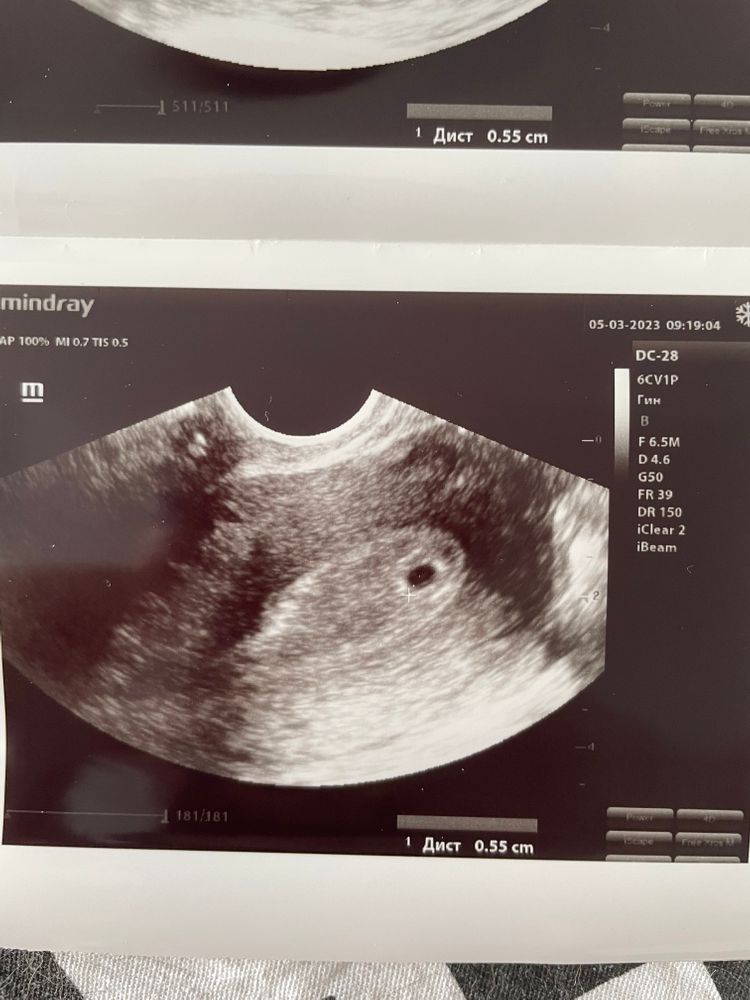

Узи 14 дпп

Ага у меня тоже на 14 дпп был один пя 😂😂😂а потом сюрприз !)))